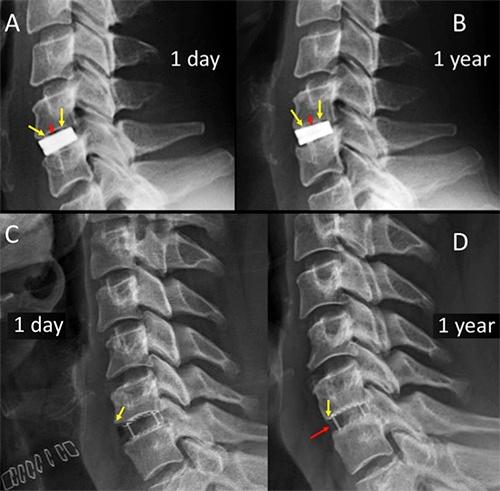

Poly-ether-ether-ketone (PEEK) cages have lower modulus of elasticity when compared with Titanium (TTN) cages. This suggests that PEEK-cages could show a lower rate of subsidence after anterior cervical discectomy-fusion (ACDF) and might lead to a lower loss of correction. We investigated the one to five year-results of standalone PEEK-TTN-porous coated cages in a patient cohort from 2014 to 2017. The patients underwent single-level ACDF for disc herniation and degenerative discopathy. Clinical and radiological outcome were assessed in 50 eligible patients after a mean of 27 months. Results: Solid arthrodesis was found in 84%. Neck disability index (NDI), and visual analogue scale (VAS) of neck and arm show comparable results to the literature. Conclusions: Clinical and radiological outcomes of ACDF with PEEK-body-cages with a porous coated surface show good bony integration. The modulus of elasticity, design, shape, size, cage surface architecture, as well as bone density, endplate preparation, radical microdiscectomy and distraction during surgery should be considered as important factors influencing the clinical results. One main advantage, over titanium cages, is the absence of MRI artifacts, allowing an excellent postoperative follow-up.

与钛(TTN)椎间融合器相比,聚醚醚酮(PEEK)椎间融合器的弹性模量更低。这表明,在颈椎前路椎间盘切除融合术(ACDF)后,PEEK椎间融合器可能显示出更低的下沉率,并可能导致更低的矫正丢失率。我们调查了2014年至2017年一组患者中独立使用的PEEK-TTN多孔涂层椎间融合器1至5年的结果。这些患者因椎间盘突出症和退行性椎间盘病接受了单节段ACDF。对50例符合条件的患者在平均27个月后进行了临床和影像学评估。结果:84%实现了坚固的椎间融合。颈部残疾指数(NDI)以及颈部和手臂的视觉模拟量表(VAS)结果与文献报道相当。结论:采用多孔涂层表面的PEEK椎间融合器进行ACDF的临床和影像学结果显示出良好的骨融合。弹性模量、设计、形状、尺寸、椎间融合器表面结构,以及骨密度、终板准备、彻底的显微椎间盘切除术和手术中的牵引应被视为影响临床结果的重要因素。与钛椎间融合器相比,一个主要优点是不存在MRI伪影,便于进行出色的术后随访。